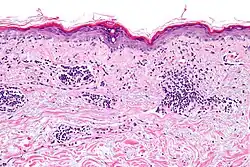

Micrograph showing vacuolar interface dermatitis, as may be seen in SLE. H&E stain.

Micrograph of a section of human skin prepared for direct immunofluorescence using an anti-IgG antibody. The skin is from a person with systemic lupus erythematosus and shows IgG deposits at two different places. The first is a bandlike deposit along the epidermal basement membrane ("lupus band test" is positive); the second is within the nuclei of the epidermal cells (antinuclear antibodies are present).